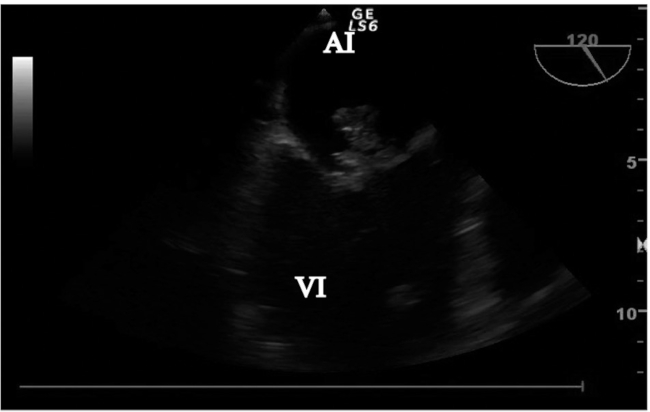

Ecocardiograma transtorácico (ETT): Tumoración heterogénea en la cara auricular de la valva mayor de la válvula mitral con una base amplia de implantación sobre la valva y gran motilidad tanto hacia la aurícula como al ventrículo en telediástole. Los diámetros son de 27 mm x 17 mm. Genera insuficiencia mitral de grado moderado, teniendo en cuenta la velocidad anterógrada y el jet que contacta con la pared posterior auricular por Doppler color. La función sistólica se mantiene conservada.

Ecocardiograma transesofágico (ETE): Válvula aórtica tricúspide. En la valva anterior de la válvula mitral, se visualiza una imagen adherida con una base amplia de implantación y ecogenicidad heterogénea de 2,67 cm x 1,47 cm de diámetro máximo, que prolapsa hacia el ventrículo izquierdo en telediástole. En la valva posterior se observa otra imagen de menor tamaño de 0,56 cm x 0,77 cm. Ambos hallazgos compatibles con vegetaciones. Por evaluación Doppler, presenta dos jets de regurgitación mitral (Figura 1).